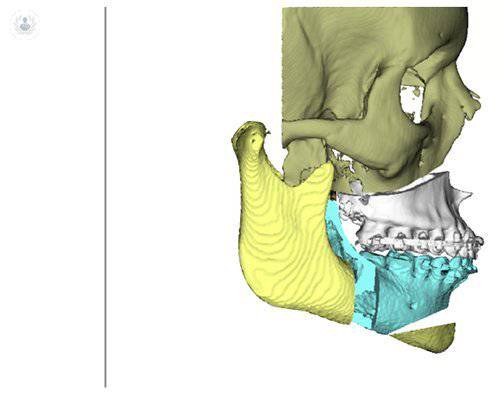

Guías y miniplacas personalizadas: un protocolo guiado para cirugía ortognática

El Dr. Joan Brunsó explica en qué medida ha ayudado la introducción de la tecnología en el tratamiento de problemas orales y maxilofaciales, como la cirugía ortognática. Conoce en qué consisten las guías y las miniplacas en cirugía ortognática, los métodos y los materiales utilizados...